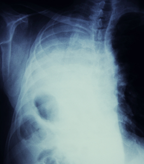

Bavituximab, a first-in-class monoclonal antibody, targets an immunosuppressive molecule called phosphatidylserine; the molecule is usually located inside a cell membrane, but is expressed externally in cells that line tumor blood vessels, making it a potential therapeutic target. Bavituximab is designed to bind to phosphatidylserine and block the immunosuppressive signal, allowing immune systems to fight the tumor.

Bavituximab is also being investigated as a first-line agent for NSCLC and for pancreatic cancer, among other indications; the second-line NSCLC use would be the first to make it to phase III trials. In March 2012, Peregrine reported that the study drug in combination with carboplatin and paclitaxel yielded a median progression-free survival of 5.8 months as a first-line treatment for stage IIIb and stage IV NSCLC, vs 4.6 months with carboplatin and paclitaxel alone. In one other phase I study that is currently recruiting patients, investigators will test bavituximab in combination with pemetrexed and carboplatin in previously untreated stage IV NSCLC.